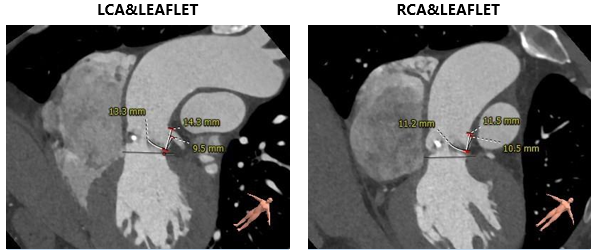

主动脉根部测量

CT特点:三叶式主动脉瓣,瓣叶轻度钙化,钙化主要位于无窦瓣叶边缘及左右窦交界处,瓣叶显著增厚伴左右窦部分融合;瓦氏窦、窦管交界内径偏小,升主动脉内径可;右冠开口高度可,左冠偏低,瓣叶冗长;非横位心。

瓣上测量

瓣上测量:瓣叶钙化较轻、增厚显著,瓣膜锚定难度稍高;左右窦交界纤维性融合存在一定限制。